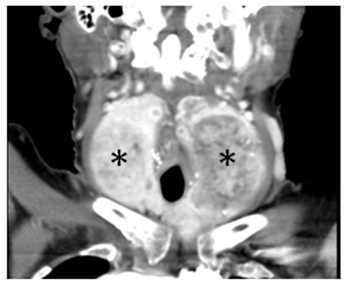

Laboratory testing reveals a TSH 1.14μU/mL (0,35-5,28). Chest radiography does not show tracheal deviation. Gastroscopy does not present esophageal alterations. Cervicothoracic CT shows a multinodular goiter with posteromedial spreading of both lobes that compress faryngoesophageal union and proximal esophagus (black arrows in Figures 1 and Figure 2). Also, larynx and trachea are displaced forward (white arrows in Figures 1 and Figure 3). Right thyroid lobe measures 5,2x4,9x7,8cm. Left thyroid lobe measures 5,7x4,9x8,8cm. Patient is dismissed for surgery due to high anesthetic risk. Currently, patient tolerates turmix diet and fluids with thickeners. Although isolated dysphagia is an uncommon symptom in compressive goiters, whose main manifestation is dyspnea, it is important to rule out an enlargement of the thyroid gland as a cause of dysphagia even in the absence of dyspnea, dysphonia or visible goiter.

Figure 1